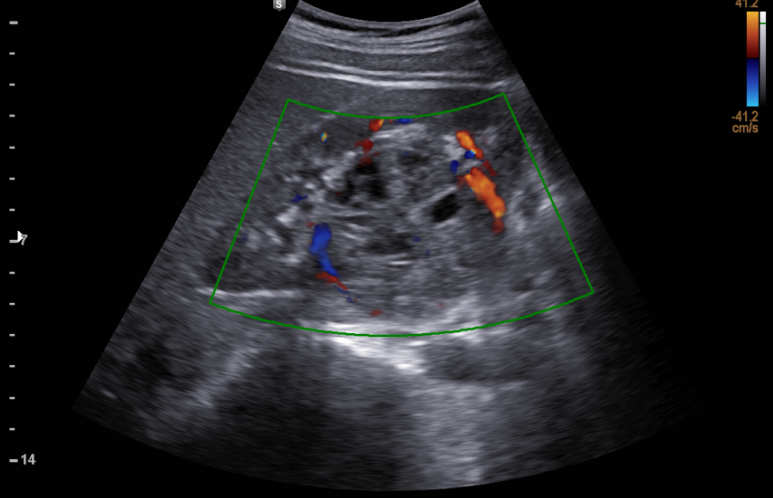

복부, 신장초음파; 흡연자에서 우연히 발견된 신장암 의증, bosniak 3

동대문구 답십리 우리안애, 우리안愛 내과, 초음파 클리닉, 영상의학 클리닉, 내과 전문의 전병연